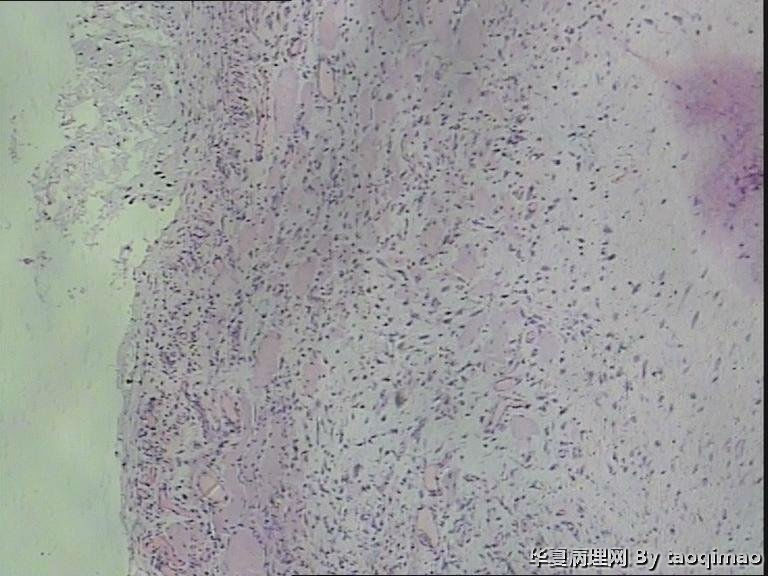

胸壁肿物

结节性筋膜炎+神经节样细胞+肌肉浸润=增生性肌炎。

考虑:坏死性筋膜炎,结节性筋膜炎,粘液瘤,脂肪肉瘤,神经纤维瘤等。

粗略看了下,对软组织病变不是很在行,初步印象是增生性肌炎,几个图像里小血管内皮肿胀,周围炎细胞浸润,结合临床除外血管炎或者自身免疫相关疾病。

男,54岁,右侧胸壁肿物发现1月余,取材:灰白色不规则组织一块2*1.7*0.5cm,剖面实性灰白色,质韧。